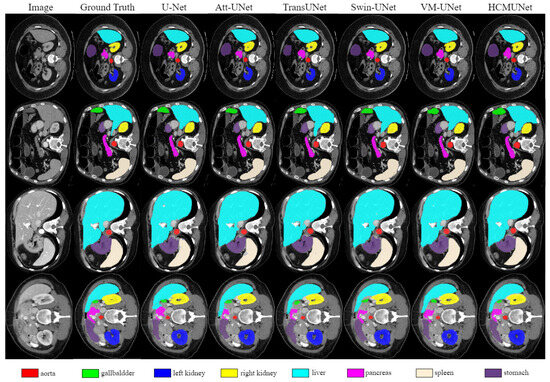

| Model | DSC | HD95 | Aorta | Gallbladder | Kidney (L) | Kidney (R) | Liver | Pancreas | Spleen | Stomach |

|---|---|---|---|---|---|---|---|---|---|---|

| U-Net [2] | 75.92 ± 2.71 | 37.55 ± 4.80 | 87.39 ± 2.87 | 67.52 ± 3.11 | 78.72 ± 2.04 | 68.87 ± 3.19 | 92.45 ± 1.26 | 51.51 ± 3.60 | 86.09 ± 3.67 | 74.82 ± 2.08 |

| Att-UNet [19] | 76.14 ± 3.32 | 33.51 ± 3.17 | 88.61 ± 2.12 | 66.40 ± 2.44 | 77.12 ± 1.49 | 71.07 ± 1.41 | 91.78 ± 2.43 | 55.01 ± 3.61 | 85.66 ± 2.72 | 73.47 ± 2.46 |

| TransUNet [43] | 76.46 ± 1.80 | 29.32 ± 4.27 | 86.55 ± 1.69 | 61.65 ± 3.40 | 79.41 ± 2.41 | 76.30 ± 2.95 | 93.13 ± 1.33 | 55.30 ± 3.29 | 84.63 ± 3.43 | 74.72 ± 1.87 |

| UCTransNet [45] | 78.24 ± 1.77 | 26.35 ± 1.38 | 86.52 ± 3.13 | 65.23 ± 2.05 | 80.69 ± 1.61 | 73.19 ± 2.58 | 93.05 ± 1.62 | 57.07 ± 2.65 | 87.55 ± 1.05 | 77.28 ± 2.48 |

| LeViT-UNet [46] | 78.82 ± 3.99 | 18.89 ± 3.99 | 85.23 ± 3.73 | 66.32 ± 1.39 | 82.68 ± 3.33 | 78.13 ± 3.37 | 93.61 ± 1.80 | 60.95 ± 2.50 | 89.00 ± 1.56 | 74.62 ± 3.68 |

| Swin-UNet [26] | 79.19 ± 2.07 | 22.07 ± 2.67 | 84.72 ± 2.61 | 66.60 ± 3.40 | 82.82 ± 1.19 | 79.41 ± 0.68 | 93.94 ± 0.75 | 59.49 ± 3.67 | 89.21 ± 2.31 | 77.36 ± 1.22 |

| HiFormer [47] | 80.55 ± 2.19 | 15.63 ± 3.41 | 87.07 ± 2.24 | 66.67 ± 2.27 | 83.92 ± 2.24 | 81.09 ± 2.91 | 94.09 ± 1.84 | 60.17 ± 2.72 | 90.76 ± 1.74 | 80.61 ± 2.31 |

| VM-UNet [12] | 80.47 ± 1.71 | 18.91 ± 2.42 | 86.84 ± 1.59 | 68.43 ± 4.13 | 85.04 ± 2.16 | 81.12 ± 2.67 | 94.11 ± 0.48 | 59.49 ± 1.78 | 87.77 ± 3.16 | 80.97 ± 2.33 |

| EMCAD [48] | 81.16 ± 2.01 | 16.72 ± 4.44 | 85.24 ± 1.80 | 67.24 ± 4.64 | 87.62 ± 0.30 | 81.38 ± 0.91 | 94.67 ± 1.77 | 61.02 ± 3.96 | 91.81 ± 2.35 | 80.30 ± 1.93 |

| HCMUNet (Ours) | 81.52 ± 1.14 | 17.83 ± 1.47 | 88.06 ± 1.63 | 69.60 ± 2.30 | 87.04 ± 0.67 | 82.35 ± 1.48 | 95.10 ± 3.71 | 59.24 ± 3.62 | 90.63 ± 1.54 | 80.76 ± 2.30 |